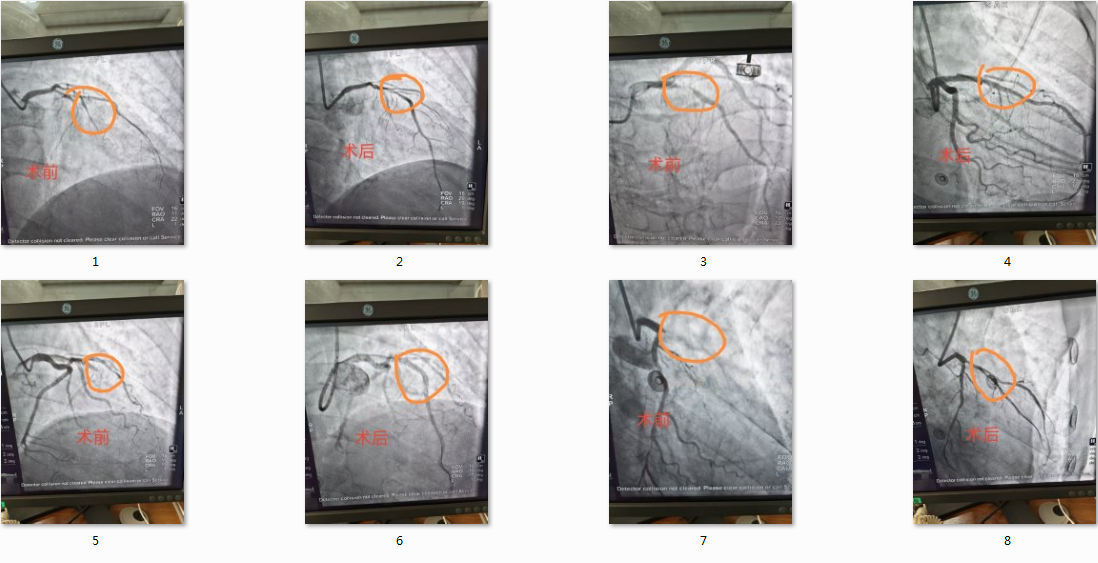

近日,阳信县中医医院介入中心联合心病科、急诊科、放射科、检验科等多学科团队紧密协作,在一周内连续为4名前壁心肌梗死患者实施急诊PCI(经皮冠状动脉介入治疗),救治工作均顺利完成。

4名患者经检查均确诊为前壁心梗,该类型病变在急性心肌梗死中病情进展较快,需及时开展救治。患者就诊后,医院胸痛中心迅速启动应急预案,急诊科快速完成病情评估、心电图检查及术前准备,介入中心联合心病科介入团队同步响应,放射科、检验科等辅助科室高效配合,为救治工作争取了时间。在多学科密切协作、无缝衔接下,4台急诊介入手术均在30分钟内完成,患者术后胸痛症状缓解,生命体征平稳,目前术后恢复情况良好。